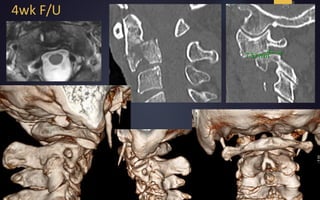

4wk F/U

Fielding Type III

White & Panjabi Type C

Fielding Type III White& Panjabi Type C